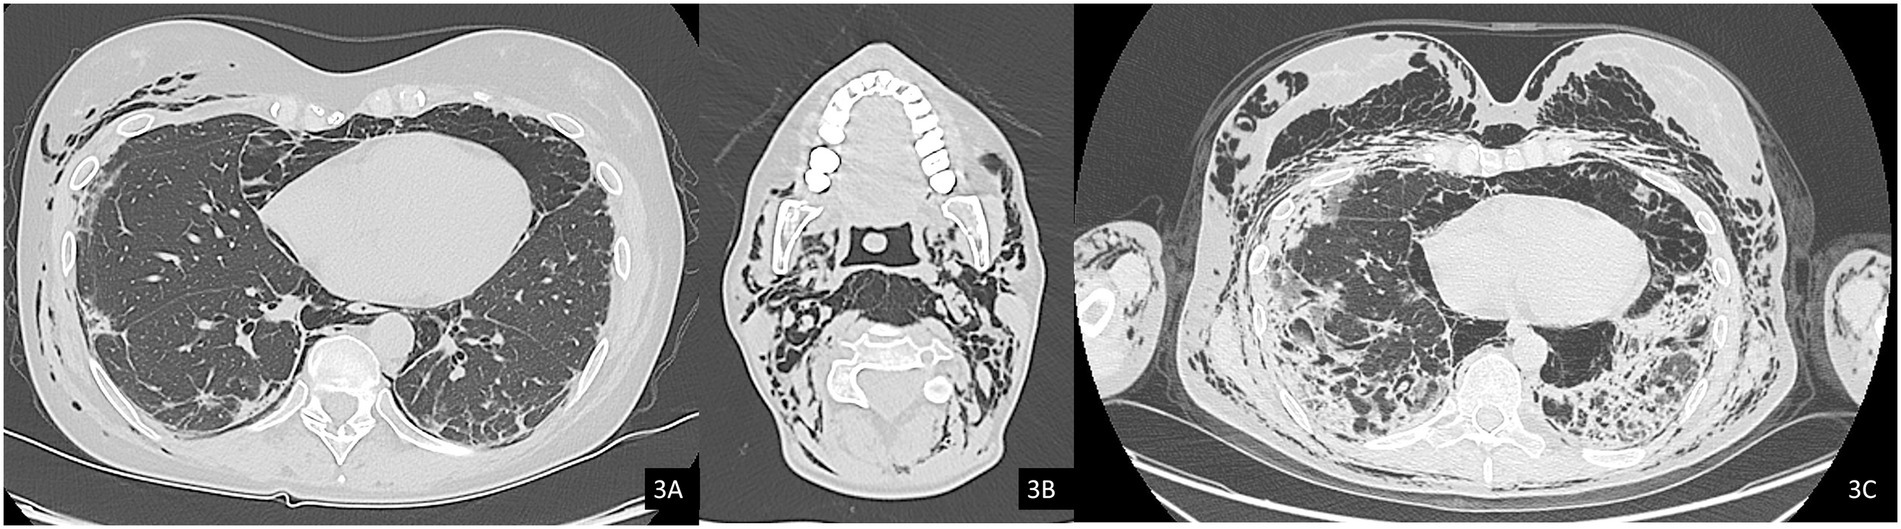

In October 2024, a Positron Emission Tomography (PET) scan conducted as part of her routine oncologic surveillance revealed findings suggestive of interstitial lung disease (ILD), spontaneous pneumomediastinum, and subcutaneous emphysema, initially without evident signs on physical examination. Subsequently, the emphysema progressively developed, with rhinolalia and subcutaneous emphysema extending to the neck. An urgent CT scan of the neck and chest confirmed a diagnosis of pneumocervicum, pneumomediastinum, pneumopericardium, and subcutaneous emphysema (Figures 3A,B). Following a pulmonology evaluation, hospitalization was deemed necessary for further management. A conservative approach was adopted following thoracic surgery consultation, and low-flow oxygen therapy was initiated. A bronchoscopy was performed to obtain microbiological samples and to identify any pulmonary lesions that could have contributed to the air formation in the mediastinum. The procedure, however, was negative for significant findings, but was complicated by pulmonary consolidation, which was treated with piperacillin-tazobactam and linezolid. An esophagogastroduodenoscopy was also performed, which ruled out the presence of an esophageal fistula. After a follow-up CT scan that demonstrated improvement in the pneumomediastinum and pneumocervicum, the patient was discharged.

Figure 3. Axial computed tomography (CT) images, lung window. (A) Evidence of pneumomediastinum and interstitial emphysema with dissection through the extrapleural spaces and soft tissues of the chest wall. (B) Axial image at the cervical level showing pneumocervicum. (C) Subsequent chest CT scan showing marked worsening of subcutaneous and mediastinal emphysema.

Subsequently, the patient was soon re-hospitalized as she experienced new episodes of acute rhinolalia and marked subcutaneous emphysema, extending from the chest to supraorbital region, with massive pneumomediastinum and pneumocervicum (Figure 3C). During this second hospitalization, two 28fr drainage segments were placed, resulting in significant air evacuation. The patient was then discharged on home oxygen therapy (2 L/min).